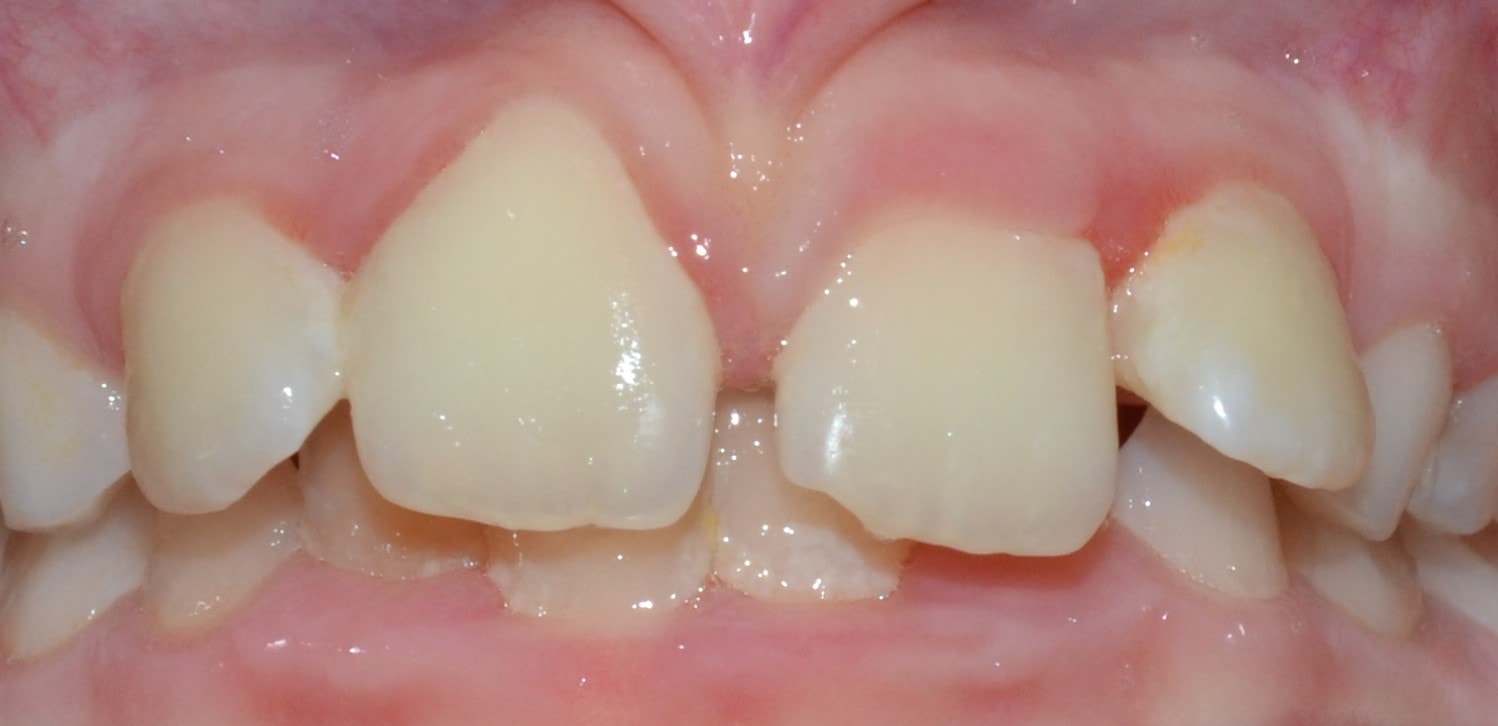

Korai vegyesfogazat

7-8 éves kor körül a gyermekek többségének korai vegyesfogazata van. Ez azt jelenti, hogy az első maradó nagyőrlők előtörtek, a tej metszőfogakat pedig felváltották a maradó metszőfogak.